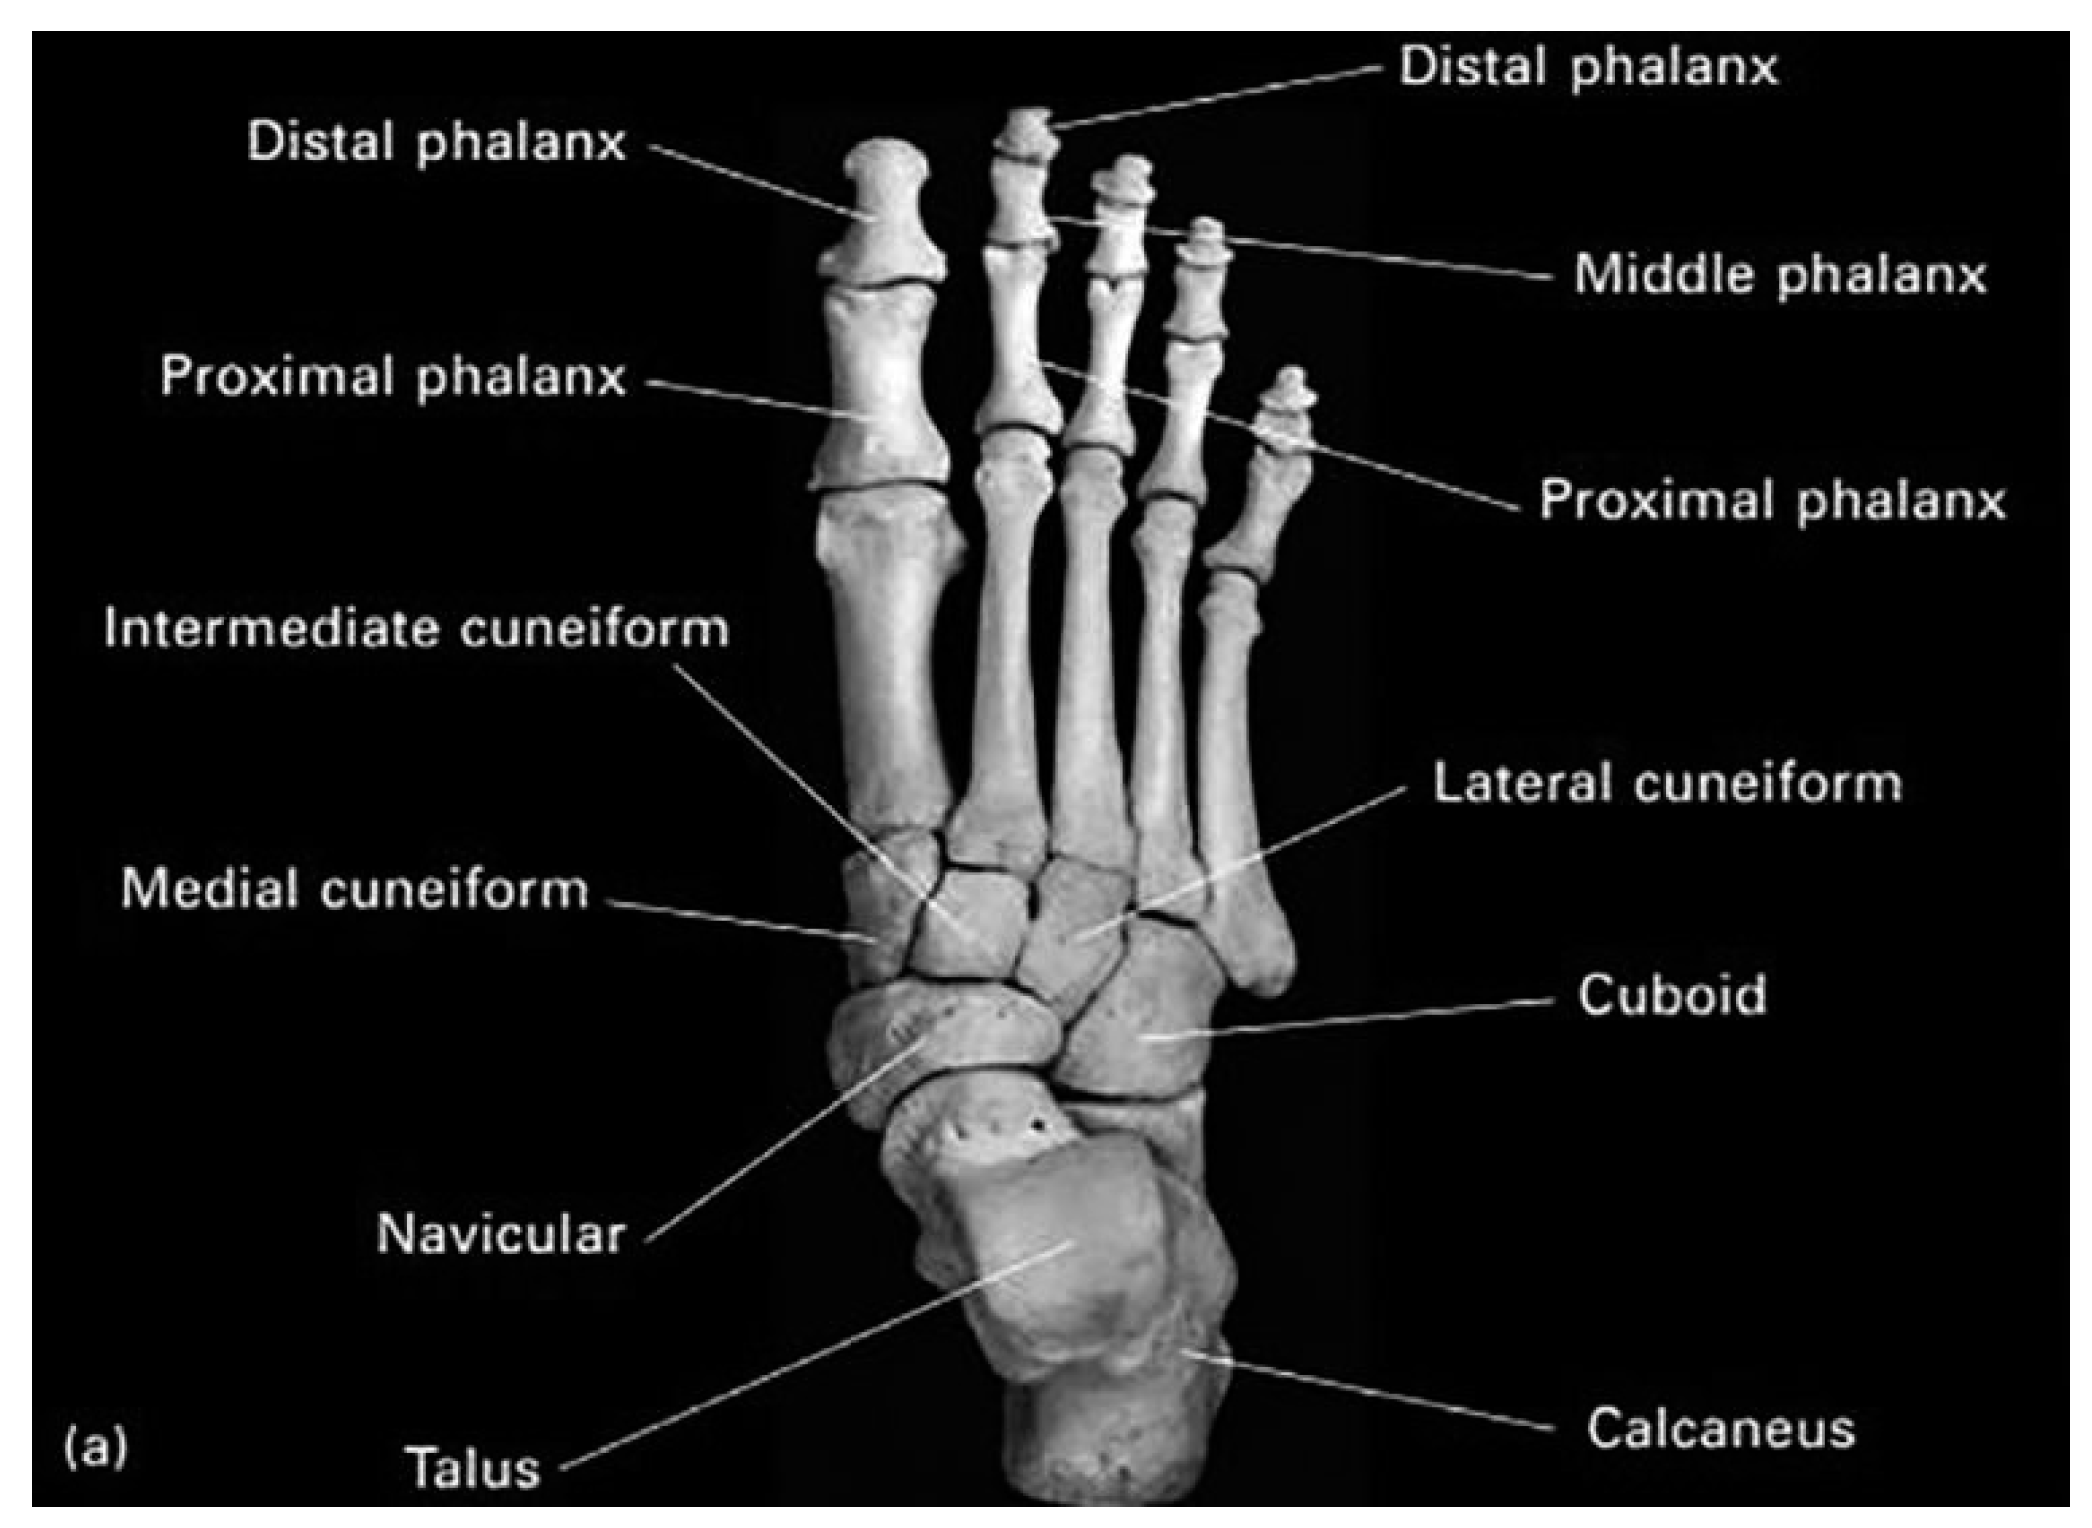

The human foot is a complex structure composed of 26 bones, 33 joints, 107 ligaments and 19 muscles. One of the main joints of the foot is the metatarsophalangeal (MTP) joint, which connects the metatarsal bones (the middle bones of the foot) to the phalanges (the bones of the toes). They allow: Flexion, Extension, abduction, adduction, and circumduction. This joint play a major role in the stance phase of the gait cycle [1].

Figure 1. Anatomy of right foot bones (Superior view) [2].